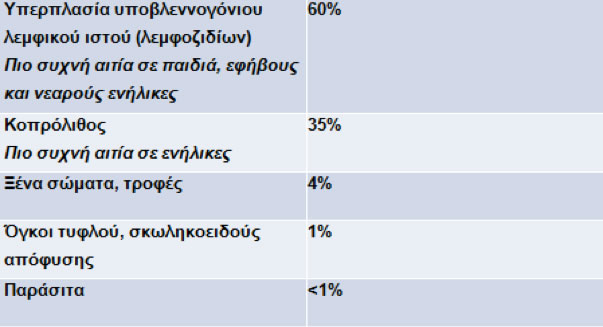

Η απόφραξη του αυλού της είναι ο κύριος αιτιολογικός παράγοντας. Τα αίτια της απόφραξης αναγράφονται στον

Πίνακα 1.

Πίνακας 1.

Αίτια απόφραξης αυλού σκωληκοειδούς απόφυσης που οδηγούν σε οξεία σκωληκοειδίτιδα